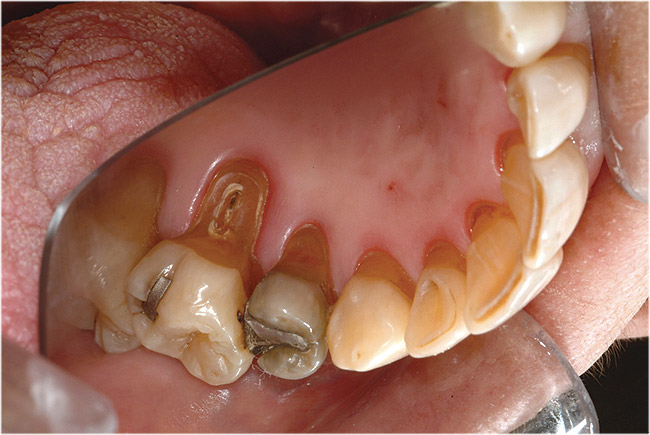

Figure  6  Erosion and abrasion in a xerostomic patient with Sjögren’s syndrome.

Figure 6

In salivary hypofunction, the lack or decrease of saliva increases the friction and effectiveness of the abrasivity of toothpaste and toothbrushing. The site-specific tooth surface loss reflects the normal protective role of serous saliva and salivary pellicle in a site-specific manner.26 Also, involuntary regurgitation and chronic regurgitation such as in hiatal hernia and gastroesophageal reflux disease (GERD) negatively affect the oral cavity because the refluxate (intrinsic acid) is low in pH (pH < 2) and readily dissolves the tooth minerals. Dental erosion can be considered an atypical manifestation of GERD. Voluntary regurgitation in cases of anorexia nervosa and bulimia also introduces gastric refluxate into the oral cavity and causes degradation of the dental structures.27-31 Additionally, various medications with anti-cholinergic side effects (eg, psychiatric, antihypertensive, a combination of medications, etc) cause salivary hypofunction. The chronic use of medications that are low in pH (liquid, chewable tablets, or inhaler forms) has a detrimental effect on teeth and can potentially cause erosion.